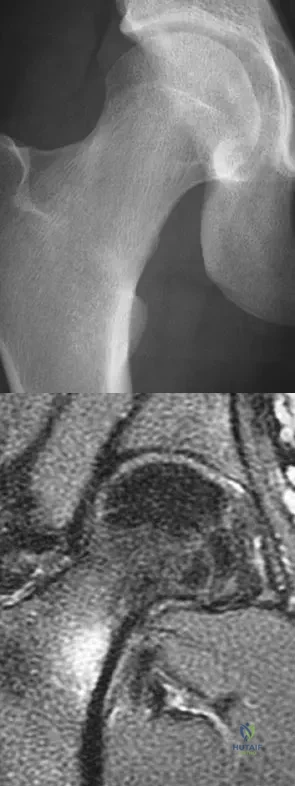

Figure 8 shows the radiograph of a 72-year-old man who has had severe pain in the left hip for the past 3 weeks. History reveals alcohol abuse. The next most appropriate step should consist of

A 21-year-old collegiate female cross-country athlete reports right hip pain that begins about 12 miles into a run, followed by pain resolution when she discontinues running. However, each time she tries to resume a running program, she experiences recurrence of pain deep in the anterior groin. A plain radiograph and MRI scan are shown in Figures 8a and 8b. Management should consist of

Explanation